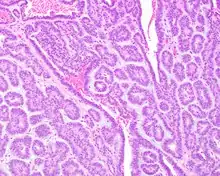

A hematoxylin and eosin stained slide of canalicular adenoma showing multifocality

Canalicular adenoma growths are usually small at the time they are noticed, with an average size of about 1.6 cm.[1] Their histologic appearance is very distinct, with a channel-like pattern between cords and ribbons; the pattern has been described as resembling a "string of pearls."